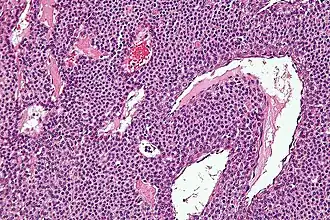

| Micrografia de um tumor glômico, tingido com H&E. | |

Histologicamente, tumores glômicos possuem uma arteríola, uma anastomose e uma vênula. Tumores glômicos são células de músculo liso modificadas que controlam a função de termorregulação da derme. Essas lesões não deve ser confundido com paragangliomas, que já foram equivocadamente chamados de tumores do glômicos. Tumores glômicos não surgem a partir de células glômicas, mas os paragangliomas sim.